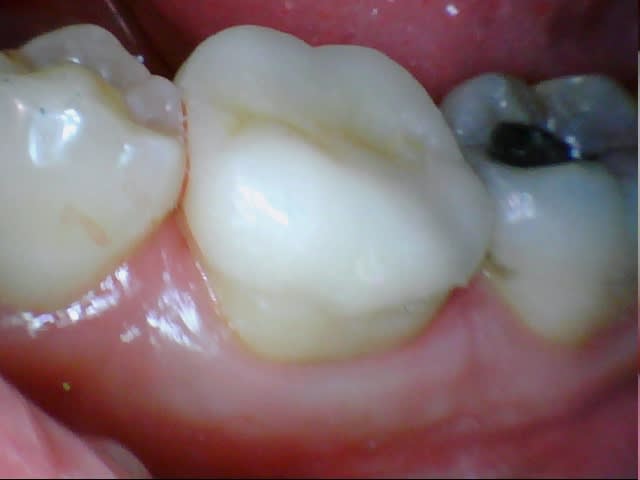

Je me suis lancé, on va voir ce que ça va donner la semaine prochaine. On mutile un peu moins c'est vrai, surtout qu'avec une prépa de dépouille pour une couronne on dézingue de fait beaucoup plus dans la partie occlusale.

J'ai tout recouvert en occlusal avec congé large.

Mis-à-part que les photos sont celles de ma cam (Chinese inside) qu'est-ce que j'aurais du faire ou ne pas faire ?